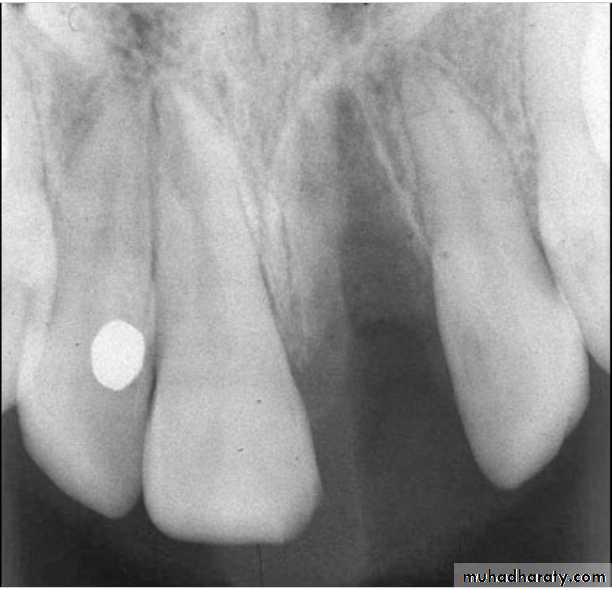

After the immobilization, a radiograph should be taken to verify the correct position of the tooth/teeth.

Associated injuries-Fracture of alveolarSocket wall

Associated injuries-Fracture of alveolar socket wall

1-Integrity of alveolus wall

2-Integrity of adjacent teeth